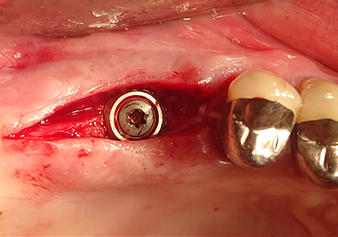

Implantation and prosthetic restoration

Situation after insertion of the implant

Fig.9: Situation after insertion of the implant (length: 10 mm, prosthetic platform: 6.5 mm) immediately before suturing.